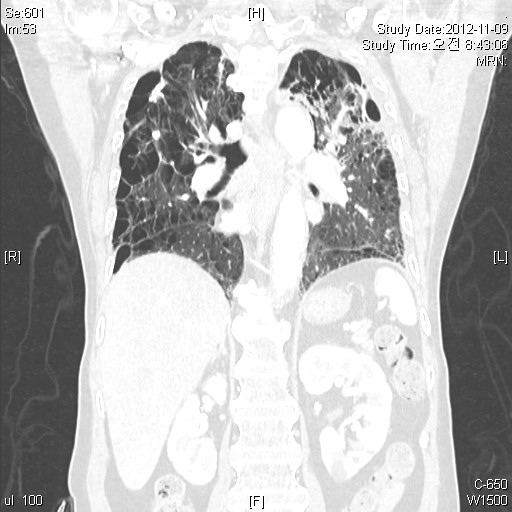

2) À̹ø Chest CT »çÁø

Compared with the previous study taken on 2012-11

Improved both lung consolidations.

No remarkable change in fibrotic lesions of both lungs.

More emphysema and enlarged bullae of both lungs.

About 17.8cm bulla of Rt. lower thorax with passive atelectasis of RLL.

Others are not remarkable